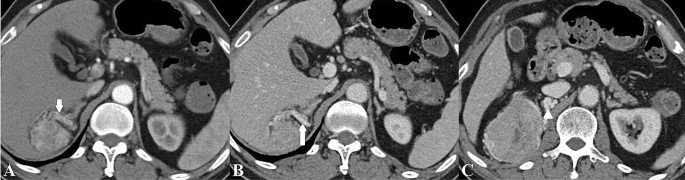

The presence of collateral vessel was defined as asymmetrically increased, usually irregular vessel within Gerota’s fascia or renal hilum of the kidney11, collateral arteries and veins were identified on the CMP and NP images, respectively (Fig. 2). The following imaging features were recorded: tumor size (maximal diameter), tumor location, the presence of calcification, necrosis, perirenal fat invasion, renal sinus invasion, renal vein invasion and thrombus (Fig. 3)8,32. Tumor attenuation and the tumor-to-renal contrast were quantitatively assessed. For heterogeneous lesions, a round or elliptic ROI was placed in the area that had the greatest degree of enhancement of the renal tumor in the CMP and NP; for homogeneous lesions, ROIs were placed in the center of the renal tumor33. The ROIs measured approximately 0.2–1 cm2 and were consistent in size and location on the unenhanced phase, CMP and NP images32. ROIs were also placed in the adjacent normal renal cortex for normalization33. At least three measurements were performed for each lesion and renal cortex on three CT scans, with averaged results34. The tumor-to-renal contrast was measured by subtracting the tumor attenuation from the normal renal cortex attenuation during the unenhanced phase, CMP and NP, respectively.

A 70-year-old man with a 7.3 cm clear cell carcinoma in the right kidney. Contrast-enhanced computed tomographic images demonstrate a prominent peritumoral collateral artery (short arrow) during the corticomedullary phase (A) and collateral vein (long arrow) during the nephrographic phase (B) in the right perinephric space. The collateral vein during the nephrographic phase (C) measures 0.5 cm in diameter (arrowhead). The collateral artery originates from the right adrenal artery, and the collateral vein is present in the form of inferior vena cava.